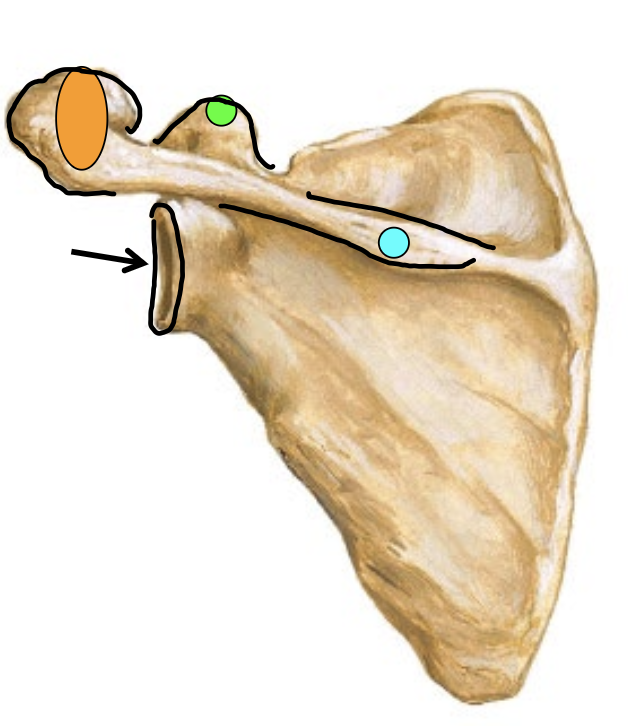

What is the arrow locating in this image?

Glenoid Fossa

What is the blue dot locating in this image?

Spine of scapula

What is the orange dot locating in this image?

Acromion process

What is the green dot locating in this image?

Caracoid process